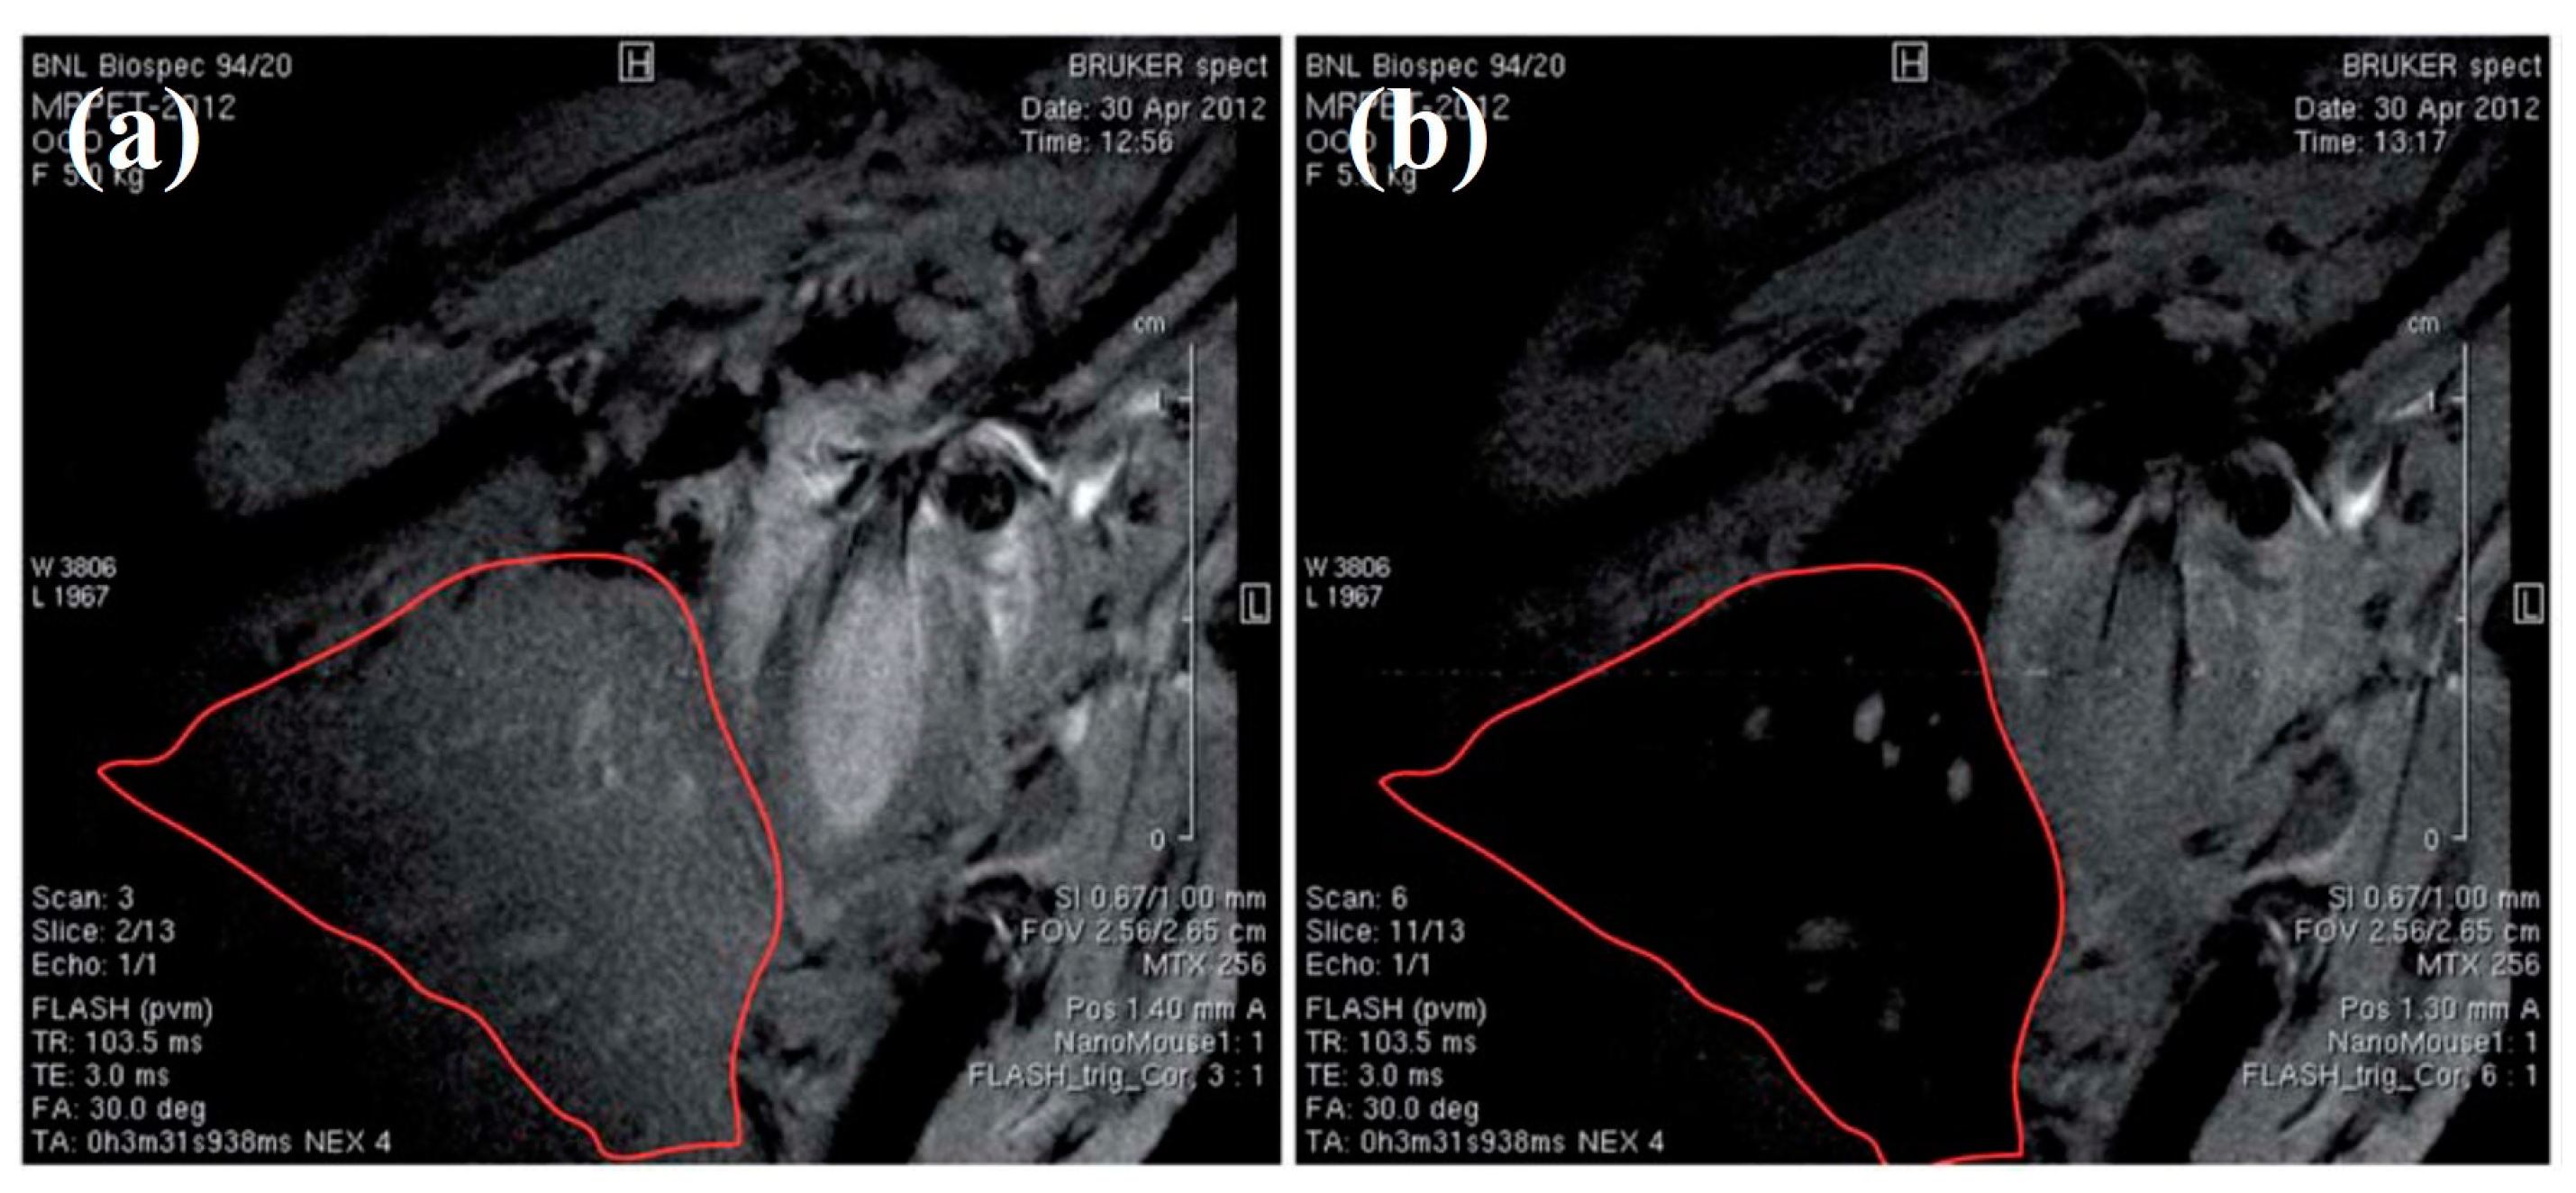

Karageorgou et al. [10,58] have synthesized 68Ga-based RIONs and subsequently have investigated their in vivo biodistribution and imaging efficiency with PET and MRI. After radiosynthesis, the RIONs exhibit a satisfactory radiolabeling yield (~70%), while after purification they show a radiochemical purity of approximately 91%. The in vitro stability of RIONs has been examined up to 2 h after incubation with human serum and has been found to be highly stable (more than 92% intact). The biodistribution results of the intravenously injected 68Ga-based RIONs in normal Swiss mice show that the RIONs are mainly found in the RES organs, where they remain up to 120 min p.i. (Figure 6a). Referring to the in vivo imaging studies performed in normal Swiss mice, both PET (Figure 6b–d) and MRI (Figure 6e–g) show identical results by demonstrating the high uptake of the RIONs in the area of the liver and spleen. Additionally, comparing the data of Figure 6e,f, it is clearly demonstrated that the contrast efficacy of the RIONs is concentration dependent. Furthermore, the MRI data prove that the contrast efficacy of the RIONs (Figure 6f) is similar to that of the non-radiolabeled IONs (Figure 6g) at a three-times higher concentration.

Figure 6.

(a) In vivo biodistribution study of 68Ga based RIONs in normal Swiss mice performed at 30, 60, and 120 min p.i. [58]; (b–d) Representative images of a mouse obtained by PET imaging at (b) 30 min, (c) 60 min, (d) 120 min p.i. [58]; T1-weighted MR image of mice injected via the tail vein with RIONs at a final concentration of (e) 0.01 mg/mL; (f) 0.1 mg/mL; (g) T1-weighted MR image of a mouse injected via the tail vein with non-radiolabeled IONs at a final concentration of 0.3 mg/mL. The MRI imaging has been performed at 6 h p.i. [10].